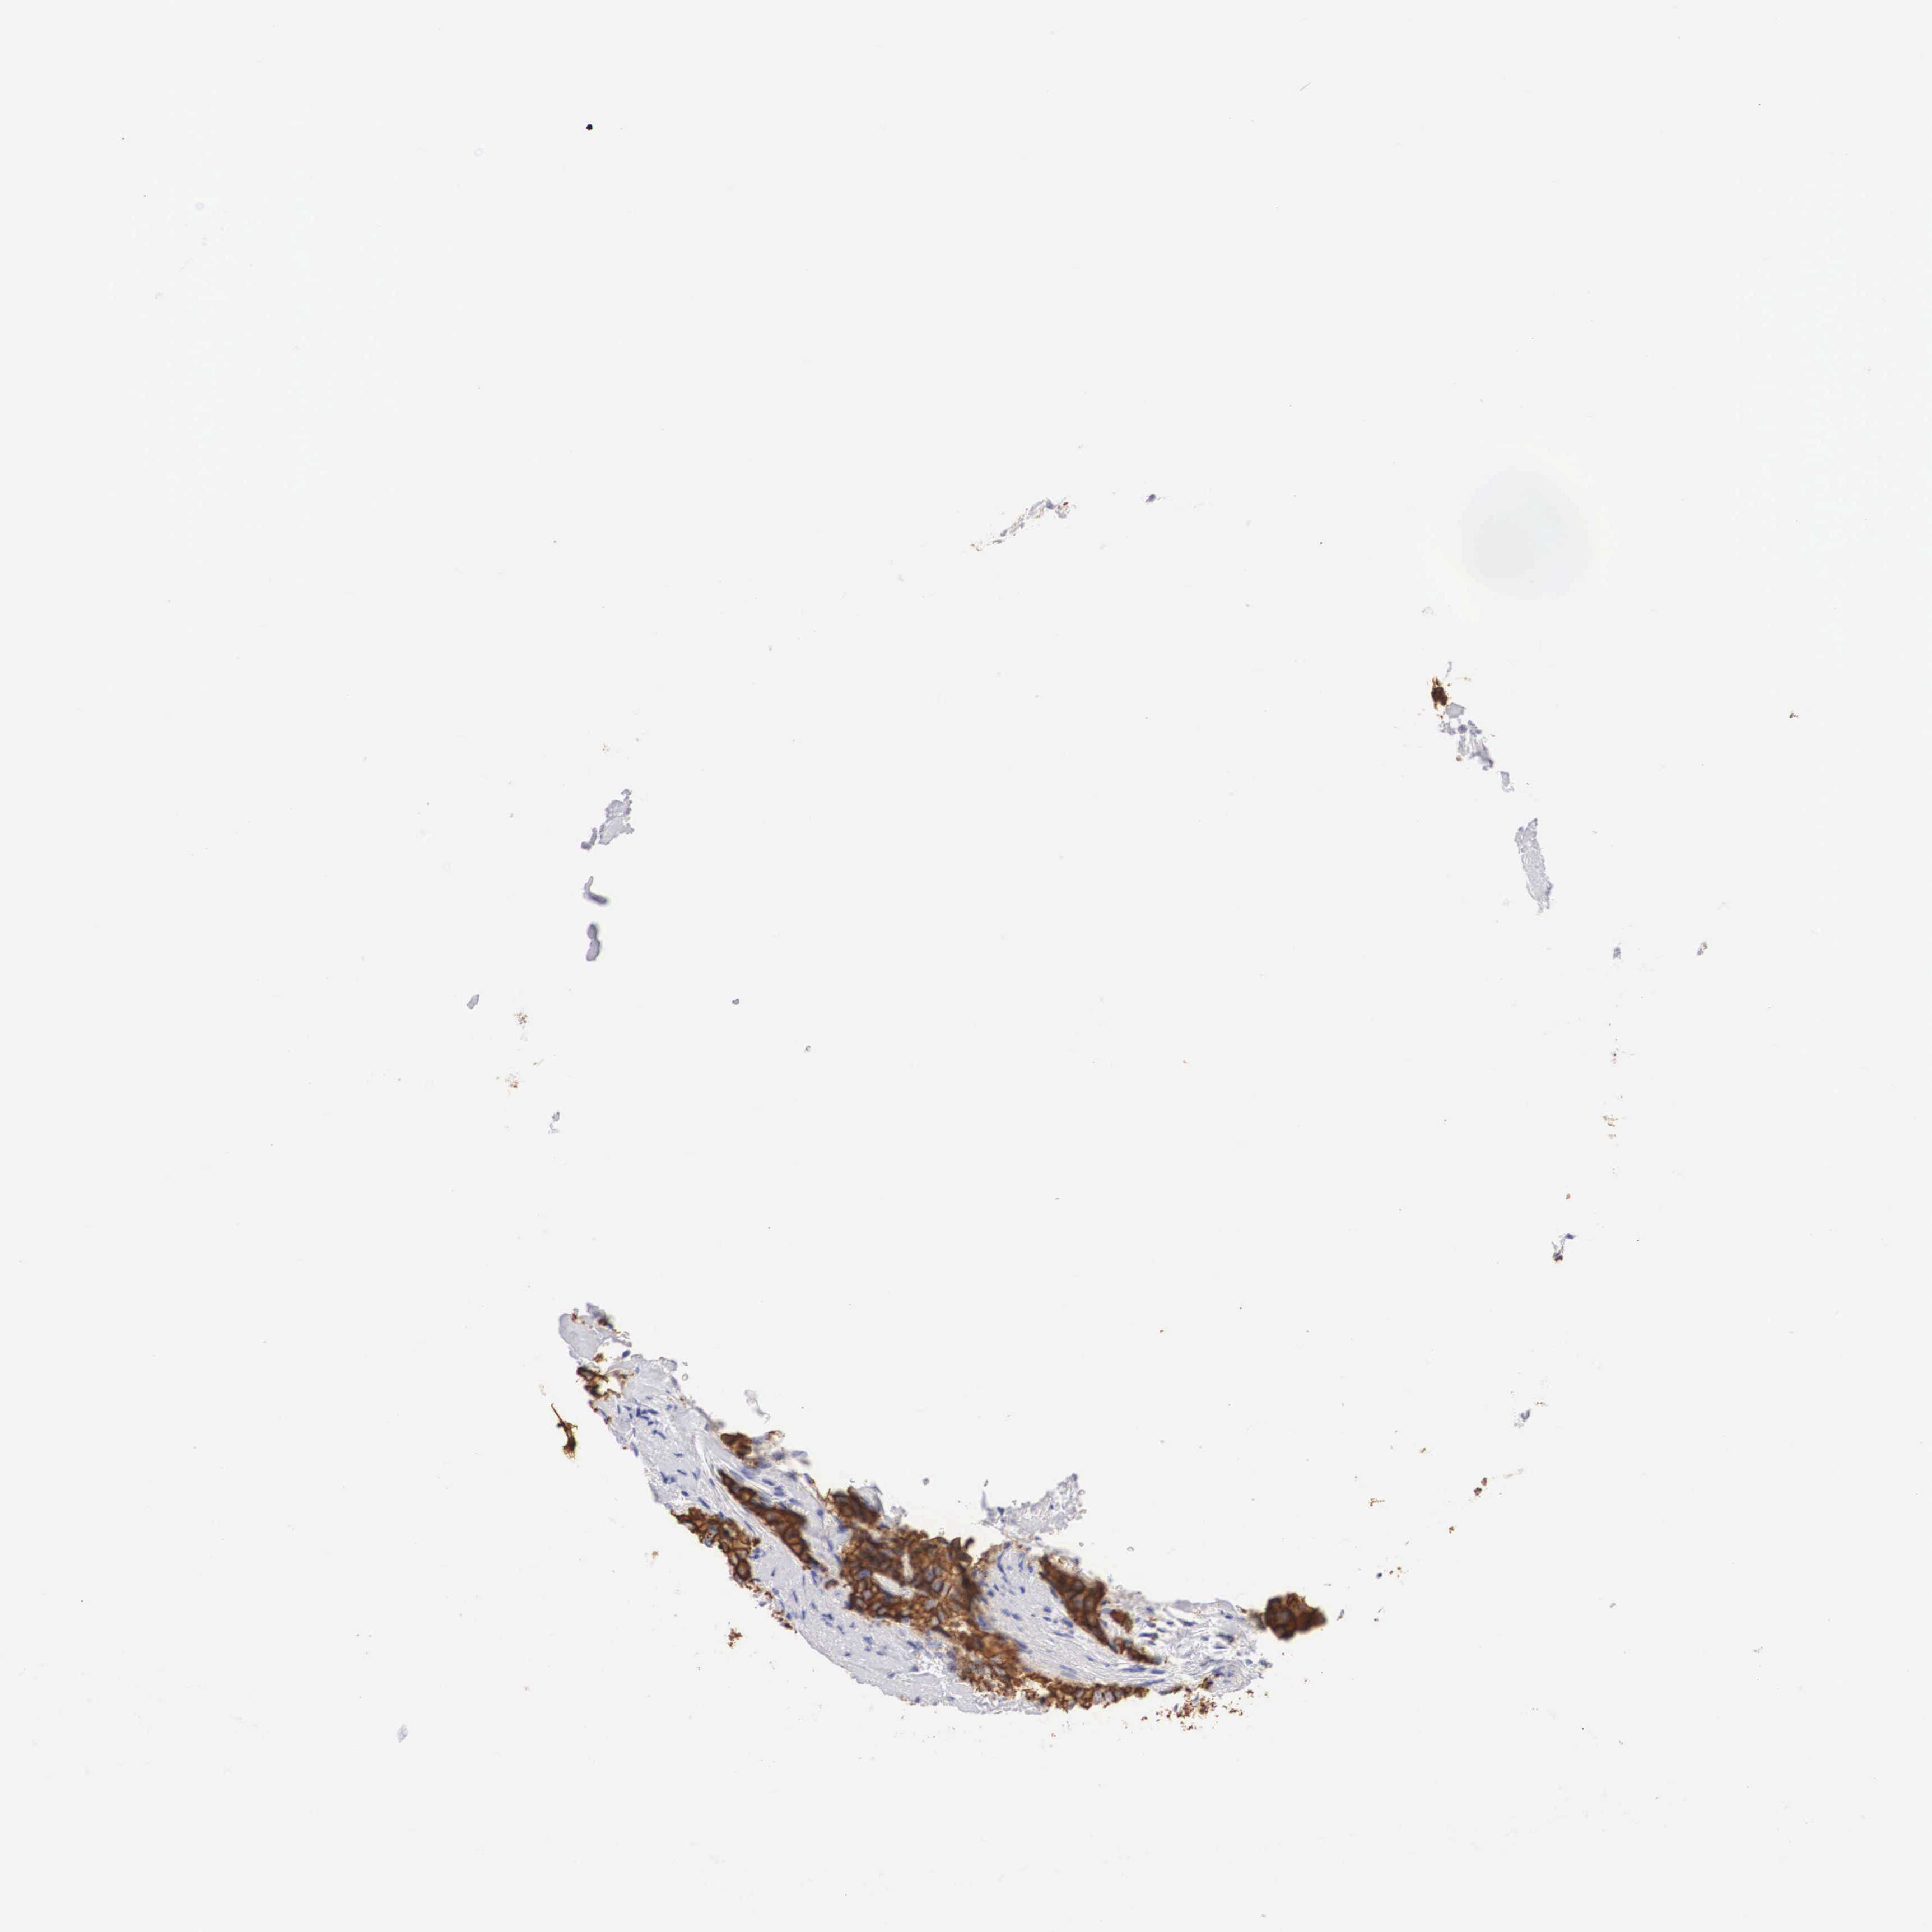

BRCA TCGA BRCA VALIDATION PROTEIN EXPRESSION

ANTIBODIES

AND

VALIDATION